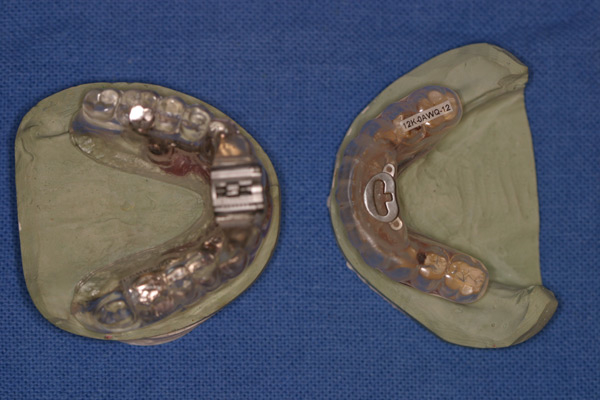

Problem: The patient came in with a broken prosthesis which broke two screws and fractured two implants. He would like it fixed.

Plan: Our plan… we removed the broken screws and kept those implants. Three more implants were placed toward the back. A titanium CAD/CAM bar with snaps for the upper prosthesis. The lower attachments were changed out for snaps as well as a new lower prosthesis.

Updating with new technology.